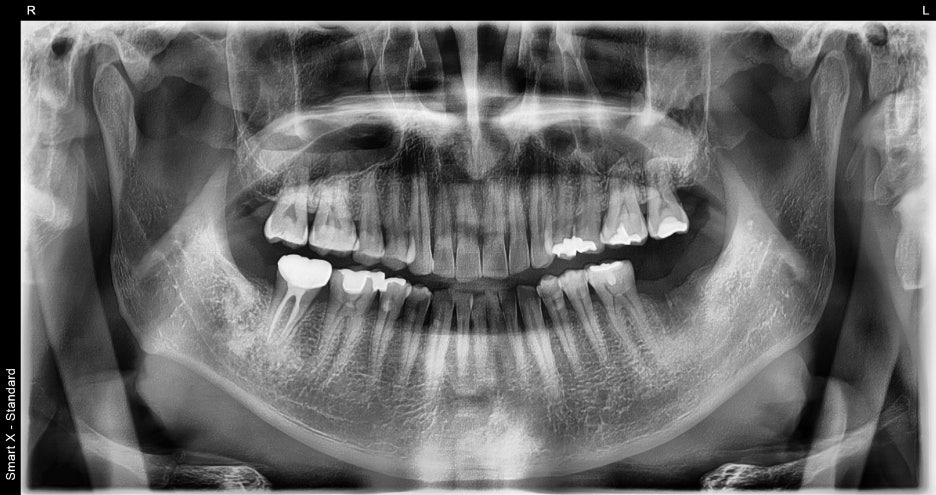

According to the panoramic X-ray,

the lower left molar had already been extracted,

and the surrounding bone condition was good,

so implant placement was confirmed to be possible without additional bone grafting.